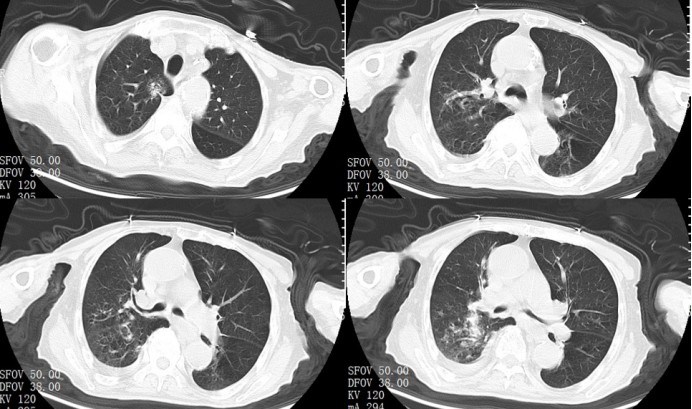

肺部CT提示:慢性支气管炎、肺气肿;两肺新发感染,右下叶明显;右侧少许胸腔积液;右下肺斜裂小结节(图1)

图片

1  患者胸部CT